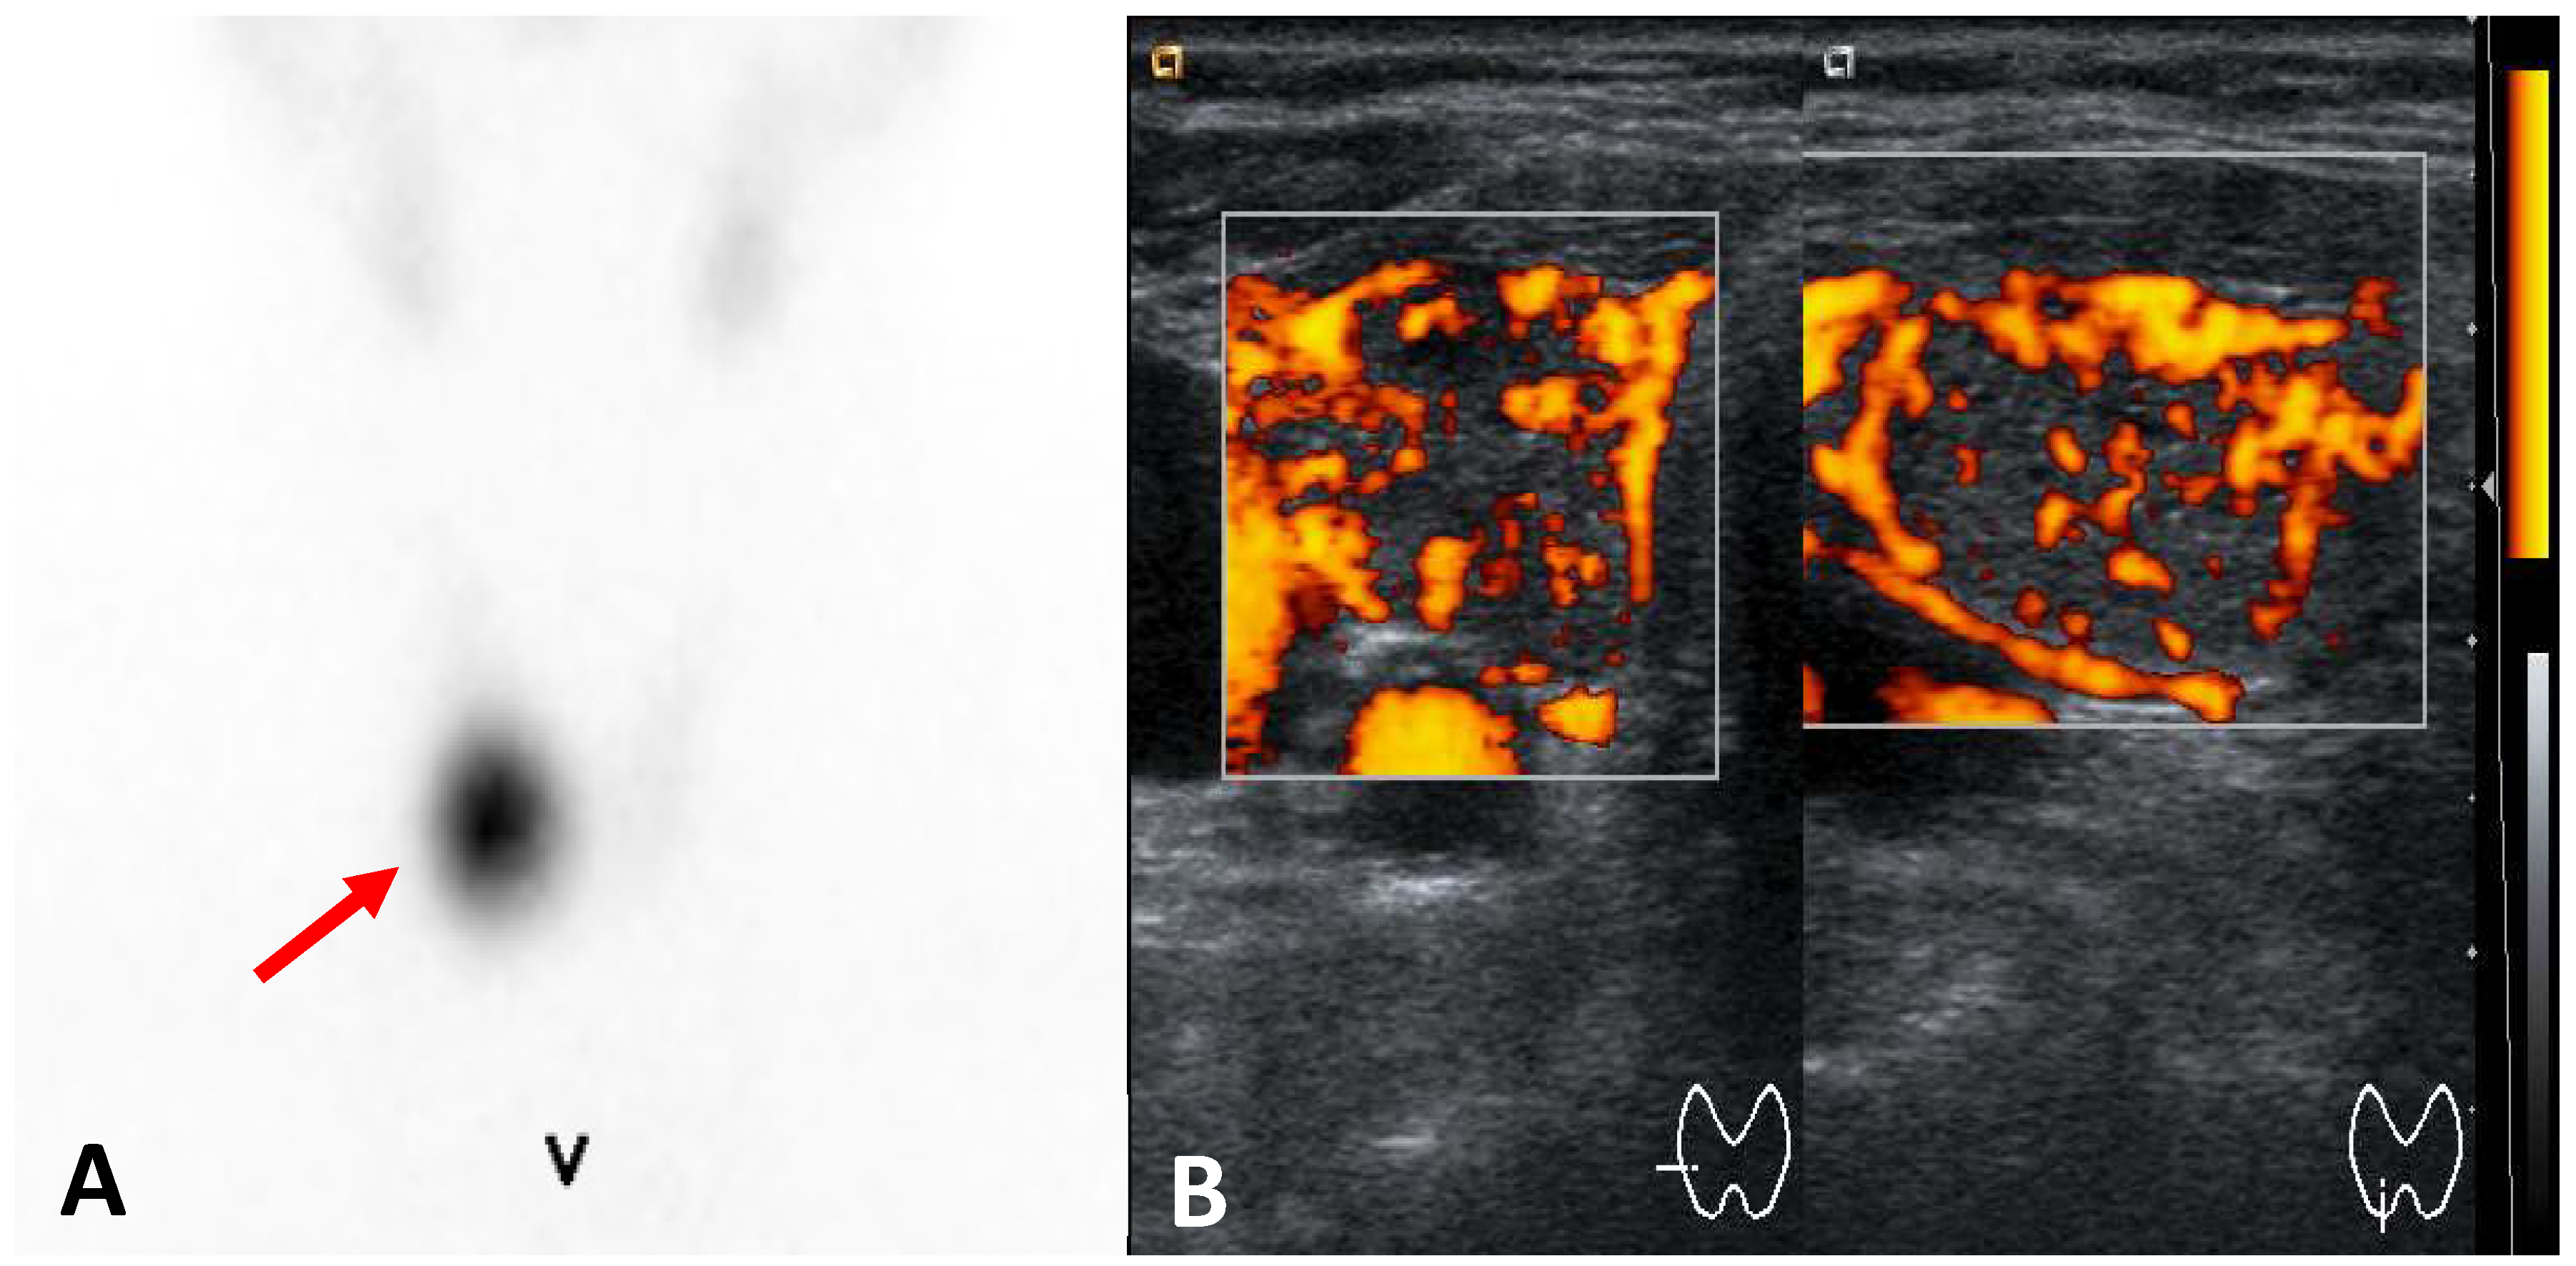

3.2.2. Unifocal Thyroid Autonomy (Solitary Toxic Adenoma)

- Hypoechoic Nodule: a solitary toxic adenoma typically appears as a well-defined, hypoechoic nodule.

- Increased Vascularity: Doppler ultrasound may reveal heightened blood flow, peripherally and within the nodule.

- Compression of Surrounding Tissue: larger adenomas may exert pressure on adjacent thyroid tissue.